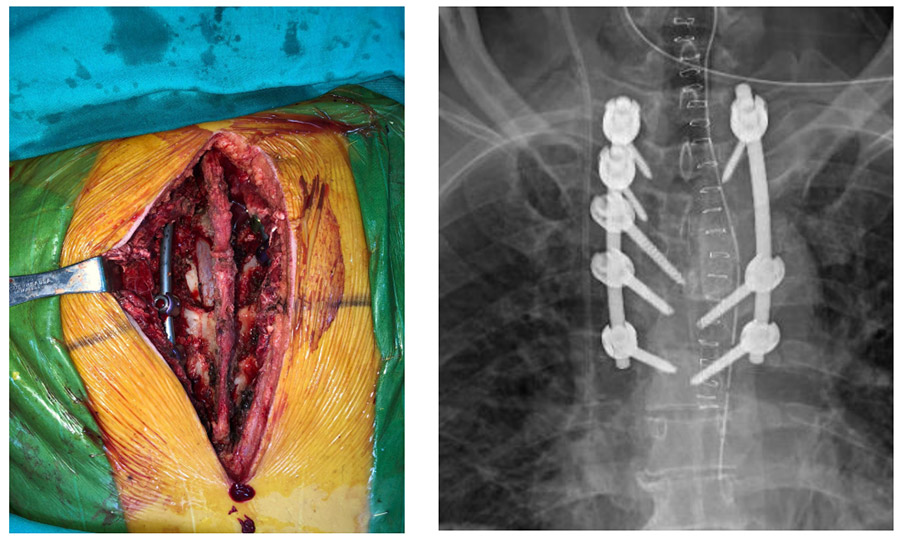

- The tumor causing spinal cord compression was completely removed (separation surgery), and stabilization was performed by instrumenting the upper and lower vertebrae with screws.

- The patient, whose pain subsided and nerve damage was repaired, was discharged walking without any problems.

- Approximately two weeks after surgery, following wound healing, the patient was referred to radiation oncology for radiotherapy.

DURING AND AFTER SURGERY: The procedure shows that the spinal cord has been freed from pressure, and the upper and lower vertebral bones have been reinforced with screws.